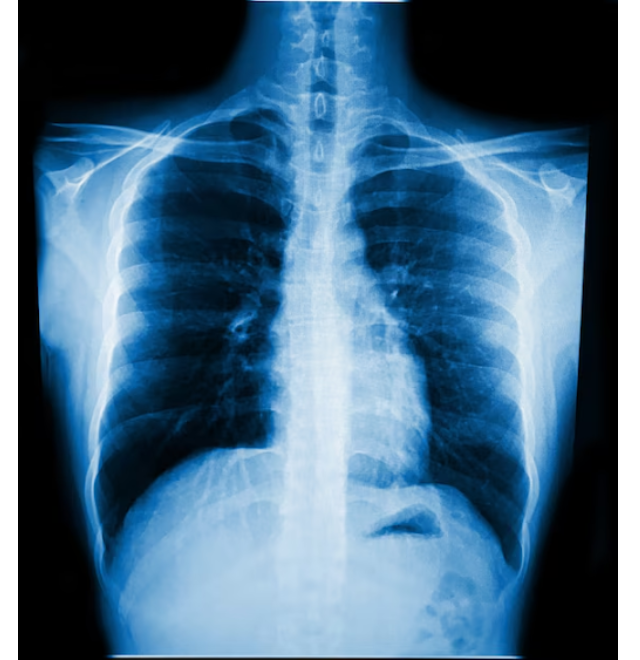

X Ray Services in Thane Clear Imaging for Confident Diagnosis

Pain and discomfort often raise questions that cannot be answered by symptoms alone. FittFocus in Thane offers X Ray services that help provide clear internal imaging to support accurate diagnosis and timely care.

X rays play a key role in identifying fractures, joint issues, alignment concerns, and certain lung or chest conditions. When discomfort persists, imaging helps remove uncertainty and allows healthcare professionals to decide the right course of action without delay. Clear results often prevent unnecessary waiting and repeated consultations.